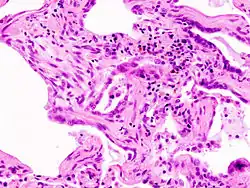

A lung biopsy may be required if the clinical history and imaging are not clearly suggestive of a specific diagnosis or malignancy cannot otherwise be ruled out. Surgical lung biopsy or via a video-assisted thoracoscopic surgery (VATS) biopsy is associated with a mortality rate up to 1-2%. A bronchoscopic transbronchial cryobiopsy, in which a camera is introduced into the airways followed by rapid freezing of an area of lung tissue prior to biopsy is associated with a lower complication rate and a much lower mortality rate compared to VATS or surgical biopsy with near comparable diagnostic accuracy.[17] There are four types of histopathologic patterns seen in ILD: usual interstitial pneumonia, non-specific interstitial pneumonia, organizing pneumonia, and diffuse alveolar damage.[10] There is significant overlap of the histopathological and radiologic features of each ILD type making diagnosis challenging; even with lung biopsy, 15% of cases of ILD cannot be classified.[10]